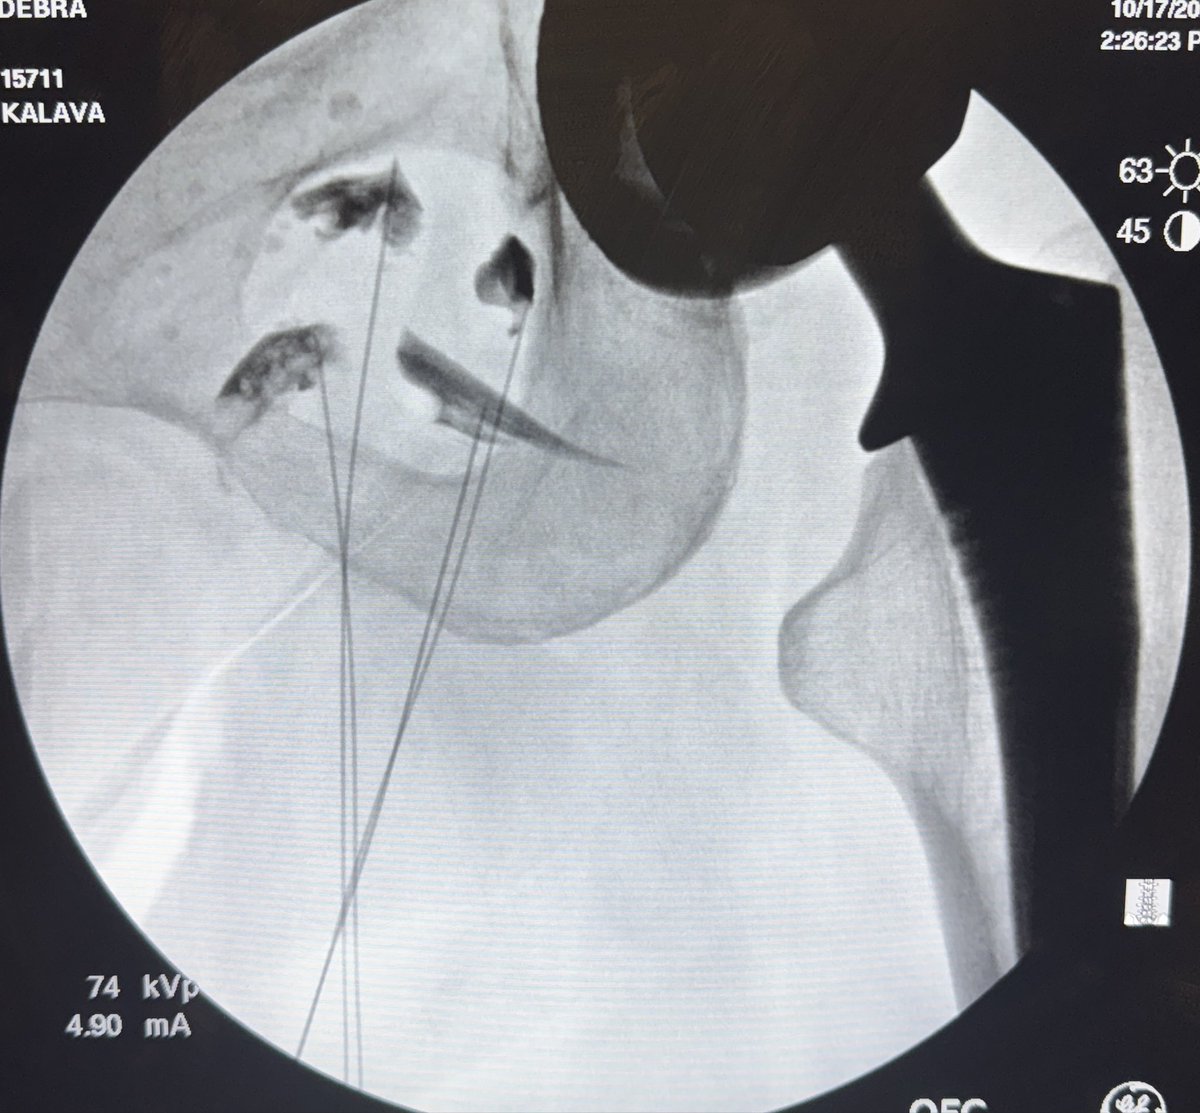

Check out the latest #APSFPodcast, all about #patientsafety in regional #anesthesia! Special thanks to Blink Medical Devices for their continued support of APSF. Don’t forget to like and subscribe! #ultrasound #anesthesiology apsf.org/podcast/290-fr…